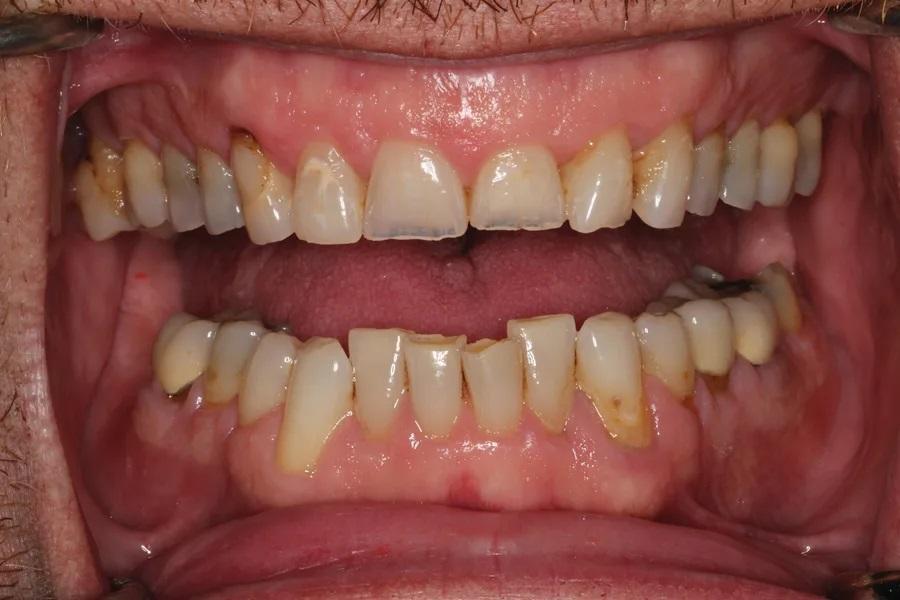

Мужчина, 45 лет. Основная жалоба — неловкость при улыбке из-за коротких, деформированных и измененных в цвете зубов. Обследование выявило гингивит с соответствующей потерей прикрепления, множественные кариозные поражения, износ зубов и реставраций (Фото 1 – Фото 3). Зафиксирован ограниченный паттерн жевания (ОПЖ), что определило умеренный функциональный риск и необходимость учета окклюзии в плане лечения.

Фото 3. Вид с ретракторами до лечения. Износ, истончение эмали, окрашивание зубов.